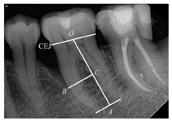

于术前和术后6个月,对患者的患牙进行数字化根尖片检查。利用根尖片分析软件测量牙位的剩余牙槽骨高度(residual alveolar bone height,RBH%),即近中(或远中)牙槽嵴顶到根尖点的距离占牙根长度的比值(图1)。

CEJ—釉牙骨质界;B点—骨缺损底;O点—釉牙骨质界中点;A点—根尖或根尖中点;C点—B向线的投影点

式中:R0为牙根长度,是釉牙骨质界连线中点(O)至根尖点(A)的距离AO,C点为牙根表面牙槽骨嵴最低点(B)向线的投影。RBH的测量与计算由一名对干预措施不知情的研究人员进行。